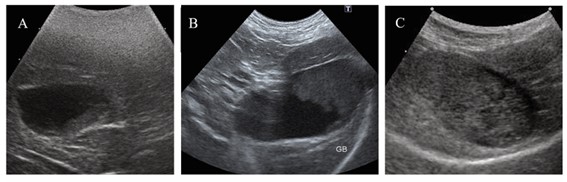

A lama biliar é identificada através de ultrassonografia abdominal, e é um achado relativamente comum, principalmente em cães mais idosos. E é classificada de acordo com quanto espaço ela está ocupando dentro da vesícula:

*a parte escura em formato redondo é a vesícula biliar e o conteúdo cinza dentro dela é a lama. A bile fluida e saudável não aparece com cor diferente no ultrassom.